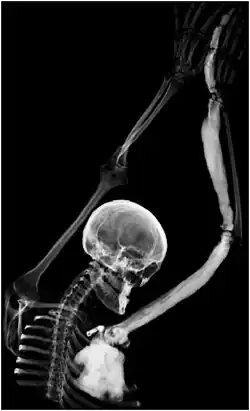

Melorheostosis is a medical developmental disorder and mesenchymal dysplasia in which the bony cortex widens and becomes hyperdense in a sclerotomal distribution. The condition begins in childhood and is characterized by thickening of the bones. Pain is a frequent symptom and the bone can have the appearance of dripping candle wax.[1]

Melorheostosis is a mesenchymal dysplasia manifesting as regions of dripping wax appearance or flowing candle wax appearance.[5] The disorder can be detected by radiograph due to thickening of bony cortex resembling "dripping candle wax." It is included on the spectrum of developmental bone dysplasias including pycnodysostosis and osteopoikilosis.[6] The disorder tends to be unilateral and monostotic (i.e. affecting a single bone), with only one limb typically involved. Cases with involvement of multiple limbs, ribs, and bones in the spine have also been reported. There are no reported cases of involvement of skull or facial bones. Melorheostosis can be associated with pain, physical deformity, skin and circulation problems, contractures, and functional limitation. It is also associated with a benign inner ear dysplasia known as osteosclerosis.[7]